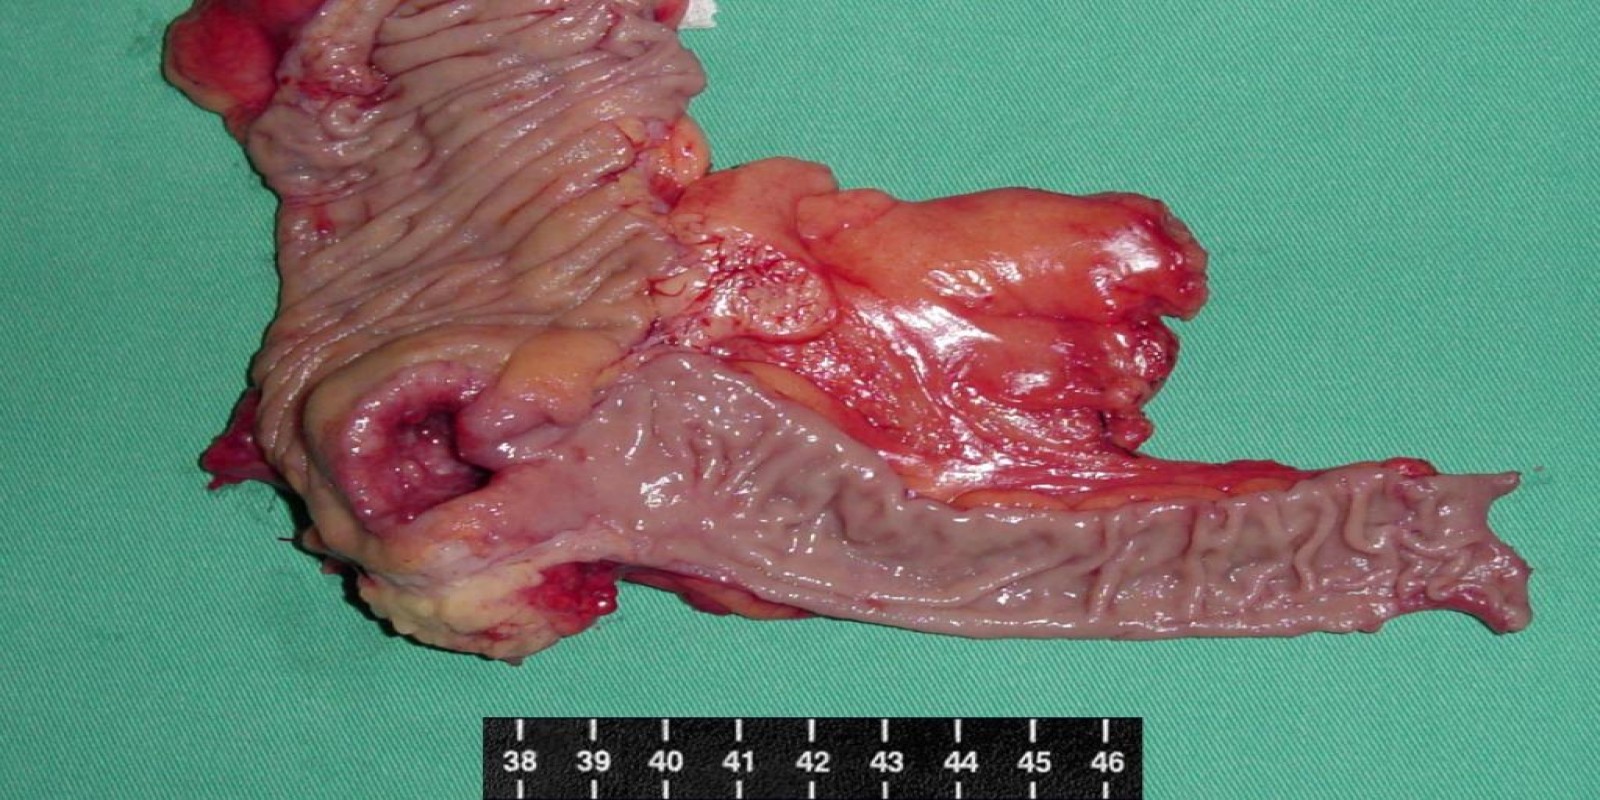

Caso Código 013B de Câncer do Cólon

Cod.: 013B